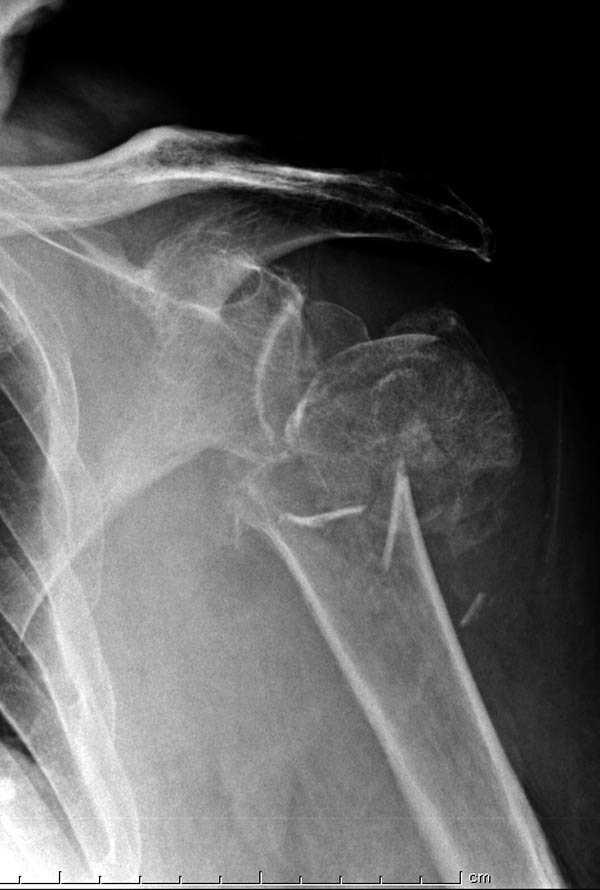

Re: Шейка плеча

дополнительные снимки по протезированию